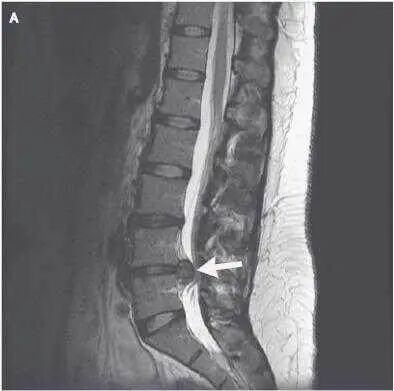

CT、核磁共振

CT、磁共振可清楚了解到椎间盘突出的位置、移动方向、大小及脊髓是否受压情况。